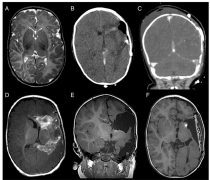

脑干胶质瘤分为两种:弥漫性脑干胶质瘤(最常见于桥脑)和局灶性脑干胶质瘤(大多位于中脑和延髓),下面我们分享一例脑干胶质瘤德国成功手术案例,前言:我庆幸,各种努...

脑胶质瘤是起源于脑部神经胶质细胞,是常见的颅内肿瘤,约占所有颅内肿瘤的45%左右。在儿童恶性肿瘤中排第二位,近30年来,原发性恶性脑肿瘤发生率逐年递增,年增长率...

多数恶性胶质瘤需手术治疗,以缓解其占位效应与相关的颅内高压症状,改善神经功能,手术应尽可能多地切除肿瘤组织,直达几乎正常的边缘。活检或少量肿瘤切除可能产...